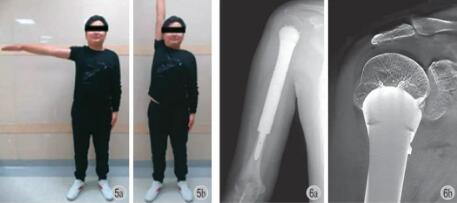

手术 2.1~4.2 h,平均 (3.3±0.7) h;术中出血量:150.0~340.0 ml,平均 (213.1±49.9) ml。所有患者均保留完整冈上肌及大部分冈下肌,小圆肌很少被保留,肩胛下肌的一部分被保留。术后随访20~63 个月,平均 45 个月。肌肉骨骼肿瘤协会评分 (musculoskeletal tumor society,MSTS) 得分为84%~99%,平均 94.4%;较术前明显改善,差异有统计学意义。系列随访中患肢平均短缩 1.64 cm,患侧肩关节平均 ROM 为前屈 84.8°,外展为 79.5°,后伸为 26.8°,内收为 16.2° (图 5)。

随访过程所有病例均未发现局部复发和远处转移。未发现假体的无菌性松动、断裂、脱位或深部感染。1 例患者术后伤口脂肪液化、浅表感染,经过分泌物培养、换药和有效抗生素治疗后伤口完全好转。1 例患者出现桡神经麻痹,术后 5 周完全恢复。术后 6 个月,用 T-SMART 观察到假体和骨之间骨长入良好,没有放射状粘连 (图 6)。术中数据以及肿瘤学和功能方面的结果 (表 4)。

图5 例 1 术后 6 个月功能情况,随访见肩关节外展功能正常

图6 例 1 术后 6 个月复查影像学,T-SMART 显示早期骨长入良好

由于手术技术和假体设计的局限性,保留肩关节的极限甚至超极限瘤性缺损重建是颇具挑战的外科难题。本中心设计的 3D 打印多孔假体特具锥状结构和缝合孔,成功实现了肱骨近端超极限瘤性缺损的关节保留重建并取得了令人满意的功能效果。本研究中,该多孔假体成功地重建了肱骨缺损并保留了肩关节。患侧肩关节平均 ROM 为前屈 84.8°,外展为79.5°,后伸为 26.8°,内收为 16.2°。功能结果显示,MSTS 平均得分 94.4%,优于其它系列 [12,20,29]。术后6 个月所有病例影像学复查结果显示假体周围放射透光度消失,T-SMART 下可观察到良好的骨长入。